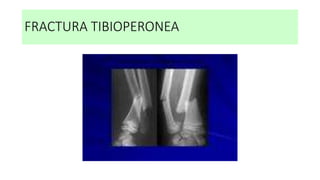

FRACTURA TIBIOPERONEA